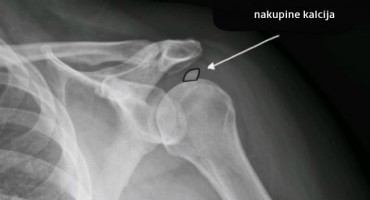

Tkivo u blizini kalcifikata zato se može upaliti i uzrokovati veliku bol. Kalcifikat se stvara u tkivu ramena odnosno u rotatornoj manšeti, onom zglobu koji je zaslužan za pokretljivost i…